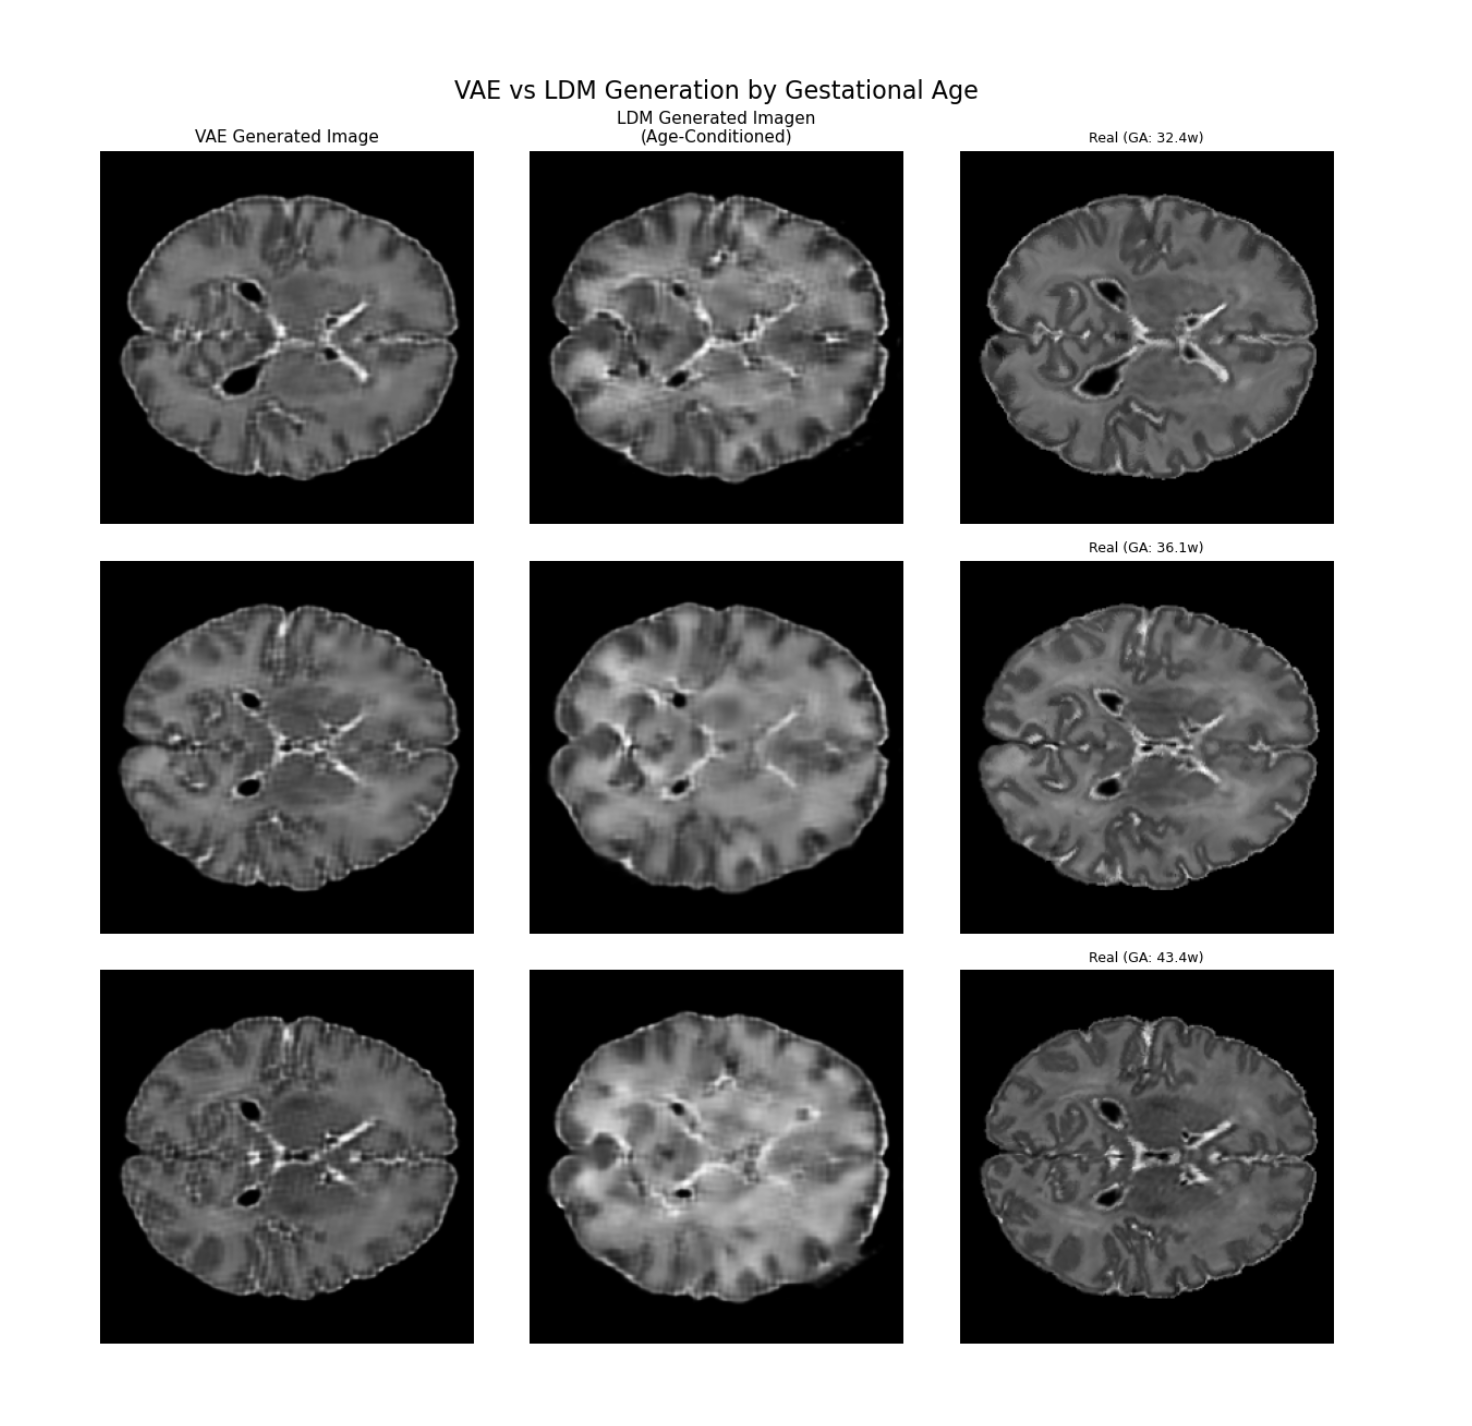

Age-Conditioned Neonatal Brain MRI Synthesis (2026)

Description:Synthesizing gestational-age-conditioned neonatal brain MRIs using Latent Diffusion Models to address severe data scarcity in pediatric neuroimaging.

I architected an end-to-end PyTorch pipeline featuring a custom age-conditioned U-Net and a VAE optimized to eliminate upscaling artifacts. I also trained an auxiliary ResNet to validate synthetic image quality via brain age estimation.

Tech Stack:PyTorch, Latent Diffusion, VAEs, ResNet, Generative models.